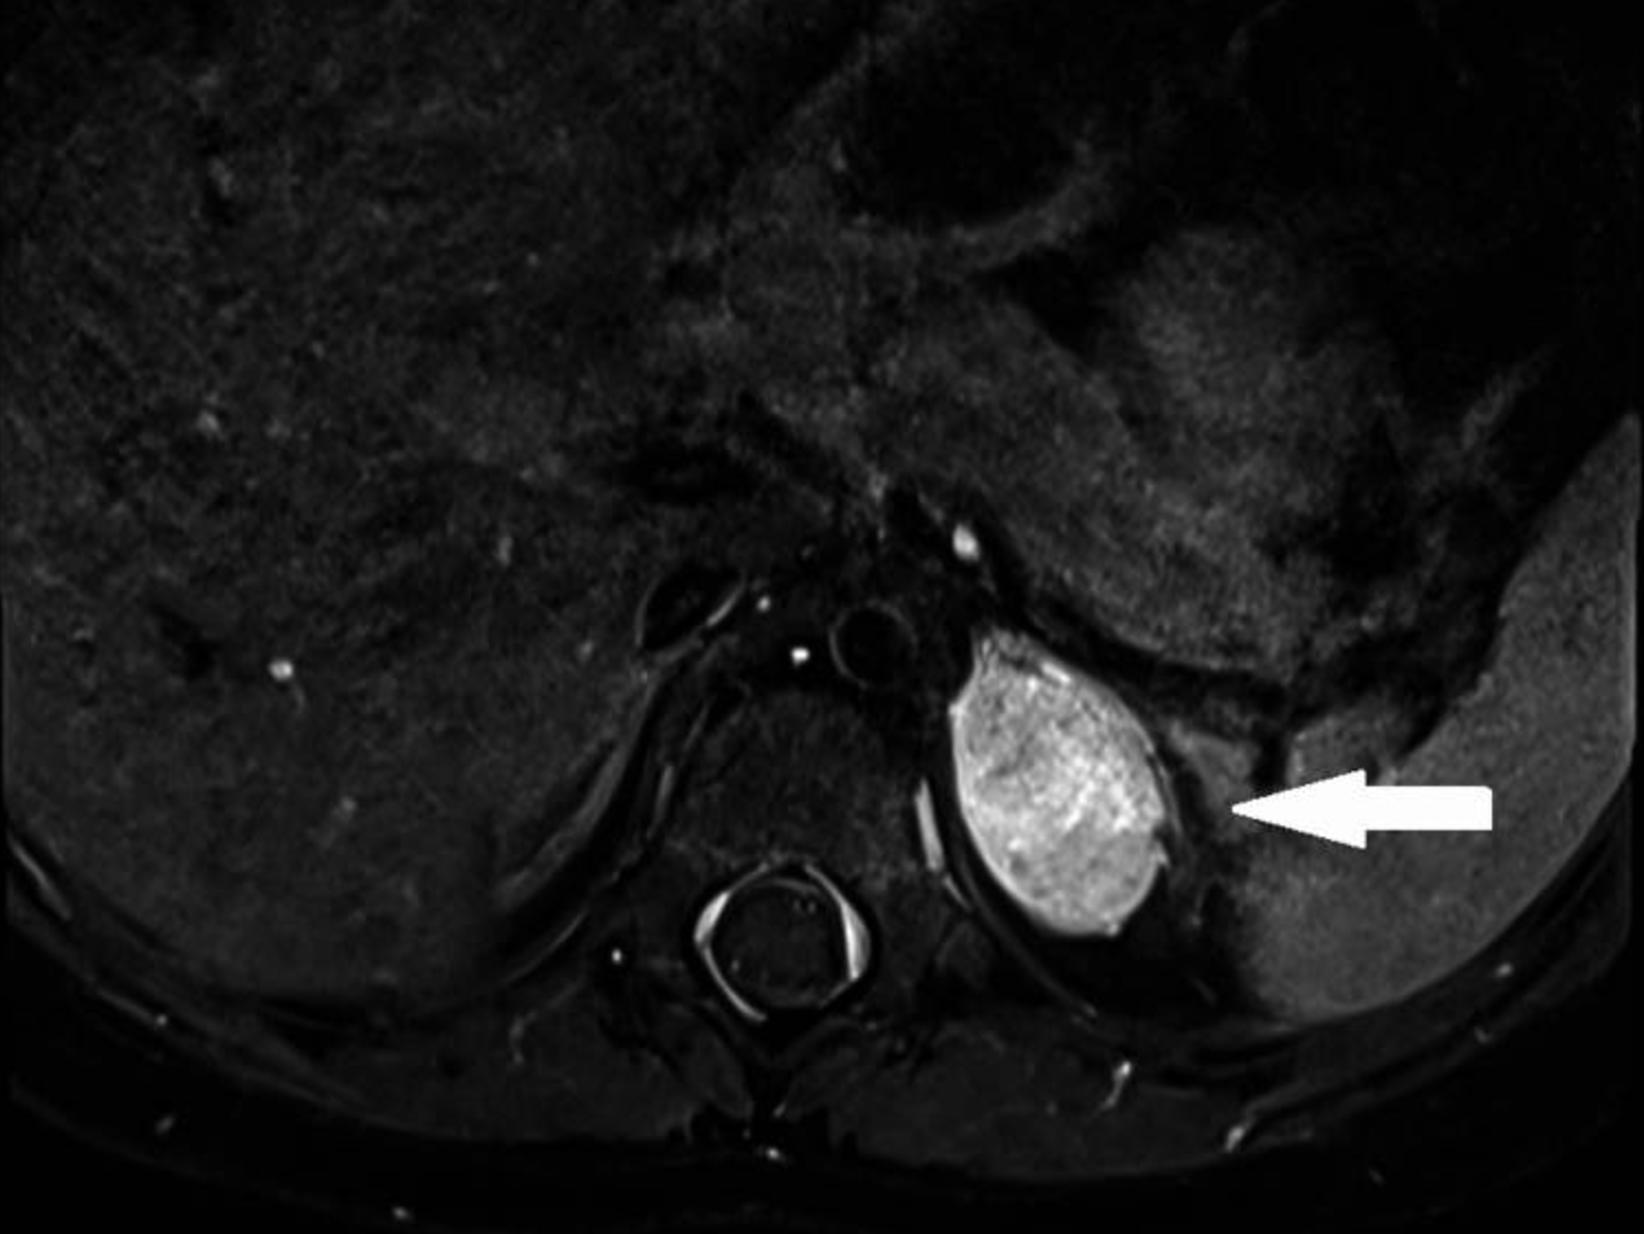

全脑和脊柱MRI检查,发现左肾上腺区肿物(图2)。胸部和腹部CT证实左肾上腺肿块约1.6×2.6×2.4厘米。在腹腔镜检查中,发现了一个4.5×3.0×2.0厘米光滑的肾上腺肿块,并将其完全切除。肿瘤的组织学表现为典型的神经节细胞瘤,多处钙化灶伴淋巴细胞浸润。根据肥胖、水平衡紊乱(低钠血症)、高泌乳素血症、多导睡眠图异常以及PHOX2B突变的缺失,患者被确诊为ROHHADNET。

图2 磁共振提示左侧肾上腺素肿物